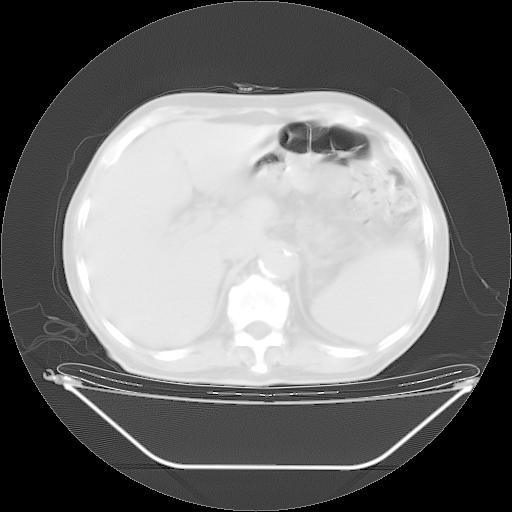

今天复查肺部CT,发现双肺广泛磨玻璃样改变。所以我把3月19日和5月9日相隔50天的肺部CT上传。请大家会诊。

5月9日肺部CT(在4月27日齐鲁医院肺部CT描述部分肺组织磨玻璃样改变,12天后肺组织广泛磨玻璃样改变)

大致读了系列胸部CT:纵隔窗无明显异常,肺窗:从4、27至今:主要是双肺中下野外带可见毛玻璃样改变,目前处于急性肺泡炎阶段,至于原因考虑1、结替组织或胶原血管性疾病所致?2、恶性疾病如恶组在肺部所致的表现或细支气管肺泡癌?3、药物或其它原因如肺蛋白沉着症所致肺泡炎目前不太可能?总之,明天就去请我院的呼吸科、感染科、血液科和临免专家会诊哈。